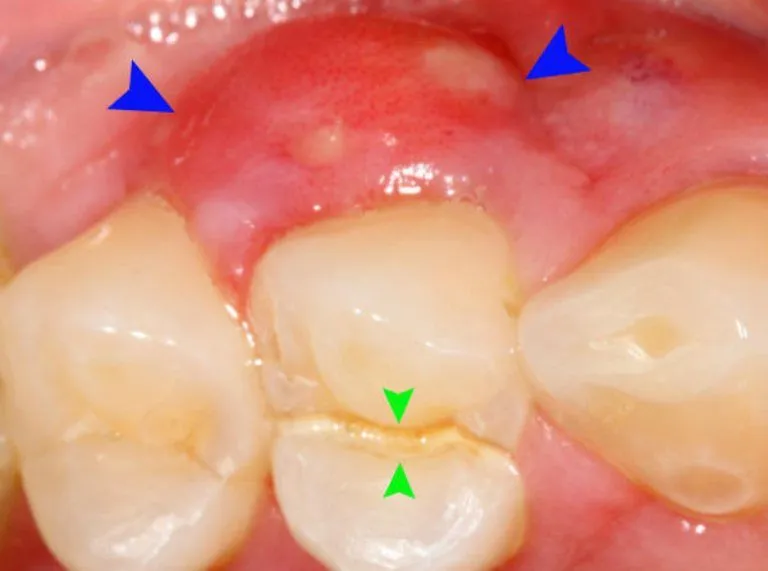

Khi trẻ bị viêm nướu răng do virus, đặc biệt là HSV-1 hoặc coxsackie, các triệu chứng thường rõ rệt và gây khó chịu nhiều. Trẻ thường xuất hiện các vết loét nhỏ (đường kính khoảng 1 đến 5mm) trong miệng. Những vết loét này có màu xám hoặc hơi vàng ở trung tâm và viền đỏ xung quanh. Vị trí và mức độ nghiêm trọng của các vết loét sẽ phụ thuộc vào loại virus gây bệnh. Các vết loét có thể xuất hiện trên nướu, bên trong má, ở phía sau miệng, trên amidan, lưỡi hoặc vòm miệng mềm. Nướu của trẻ có thể trở nên viêm sưng, đỏ chót và rất dễ chảy máu, ngay cả khi chỉ chạm nhẹ. Vì vết loét gây đau đớn dữ dội, trẻ dễ trở nên cáu kỉnh, quấy khóc, chảy nước dãi nhiều hơn bình thường và thường từ chối ăn uống, dẫn đến nguy cơ mất nước và suy dinh dưỡng. Kèm theo đó, trẻ có thể bị hôi miệng và sốt cao (lên đến 40 độ C). Các hạch bạch huyết ở hai bên cổ cũng có thể bị sưng và mềm khi chạm vào, đây là dấu hiệu cho thấy cơ thể đang chống lại nhiễm trùng. Nếu bạn nhận thấy những triệu chứng này ở con mình, đặc biệt là sốt cao và không ăn uống được, hãy gọi điện hoặc đưa trẻ đến bác sĩ chuyên khoa ngay lập tức để được thăm khám và có hướng điều trị viêm nướu răng trẻ em phù hợp.

Đối với viêm nướu răng do vệ sinh răng miệng kém và tích tụ mảng bám, các dấu hiệu thường ít cấp tính hơn so với viêm nướu do virus nhưng lại âm ỉ và kéo dài nếu không được khắc phục. Triệu chứng điển hình là nướu bị sưng đỏ, viêm tấy và trông bóng hơn bình thường. Thay vì màu hồng nhạt khỏe mạnh, nướu sẽ có màu đỏ đậm hoặc đỏ tím. Một trong những dấu hiệu dễ nhận biết nhất là nướu dễ chảy máu khi chải răng, dùng chỉ nha khoa, hoặc thậm chí là khi ăn những thức ăn cứng. Trẻ có thể cảm thấy khó chịu nhẹ, ngứa hoặc đau rát ở vùng nướu bị viêm, nhưng thường không đau dữ dội như khi có vết loét do virus. Hôi miệng cũng là một triệu chứng thường gặp do sự phát triển của vi khuẩn trong mảng bám. Đôi khi, cha mẹ có thể quan sát thấy mảng bám hoặc vôi răng (cao răng) tích tụ ở đường viền nướu của trẻ. Nếu không được xử lý, tình trạng viêm nướu này có thể tiến triển thành viêm nha chu, một bệnh lý nghiêm trọng hơn ảnh hưởng đến các cấu trúc nâng đỡ răng và có thể gây mất răng sữa sớm hoặc ảnh hưởng đến sự phát triển của răng vĩnh viễn. Vì vậy, việc nhận diện và can thiệp sớm bằng cách cải thiện vệ sinh răng miệng và thăm khám nha khoa là rất quan trọng để điều trị viêm nướu răng trẻ em hiệu quả.